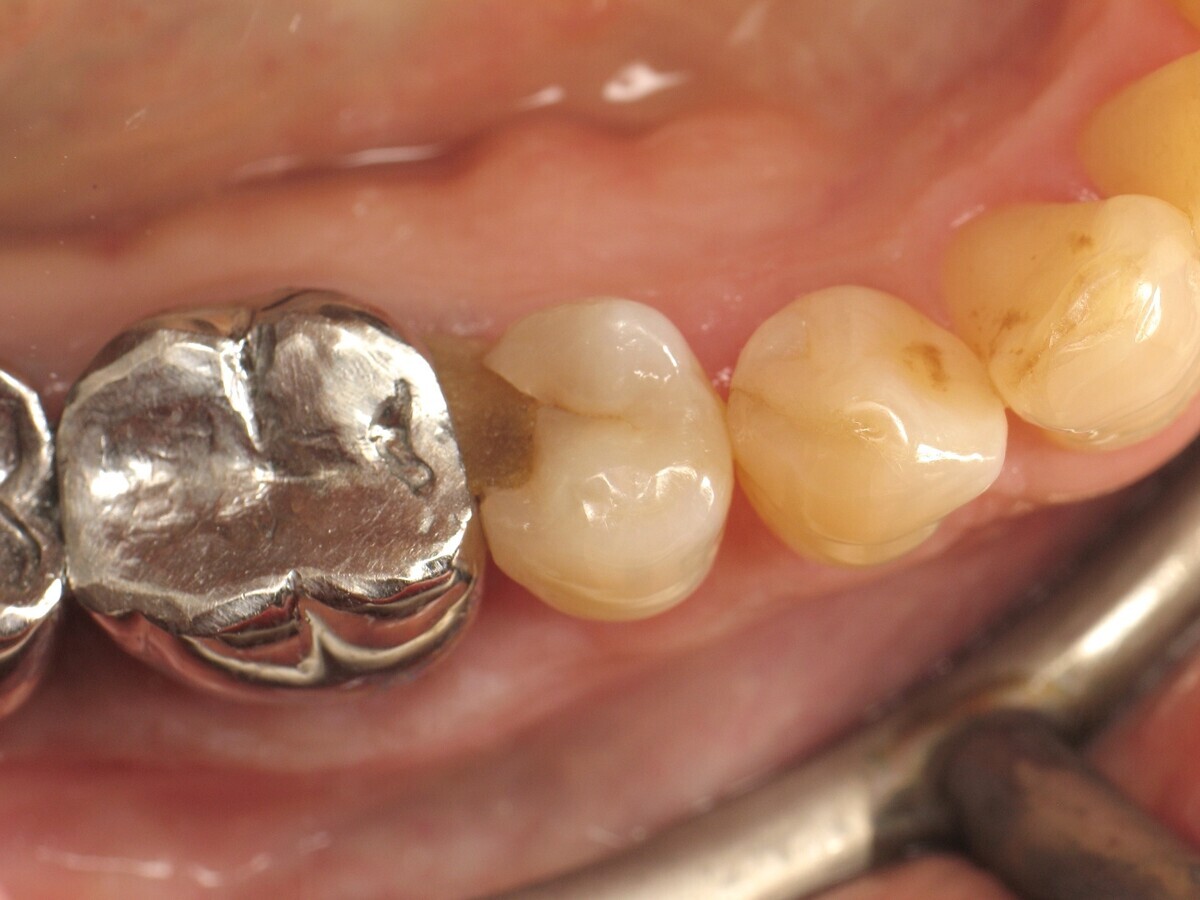

Antes y después. Izquierda: situación inicial del premolar con caries de clase II. Derecha: restauración finalizada y pulida. Fotografías: Yassine Harichane

El caso clínico descrito en este artículo se refiere a una cavidad de clase II en un premolar (45) que será restaurada con un composite termoviscoso (Figura 1).

Figura 01. Premolar con caries de clase II.

Para ajustar la oclusión, se utiliza papel articular para visualizar los puntos de contacto (Figura 20) y realizar las correcciones necesarias (Figura 21). El resultado final es muy natural (Figura 22).

Figura 20. Control de oclusión antes de los ajustes.

Figura 21. Control de oclusión después de los ajustes.

Figura 22. Restauración completada después del pulido.